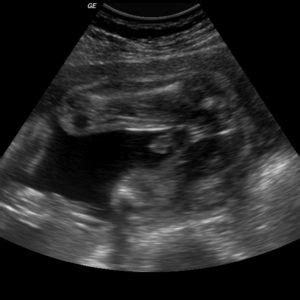

Sono a ultrazvuk sú dve z najčastejšie používaných slov počas tehotenstva. Tieto vyšetrenia predstavujú kľúčový nástroj na sledovanie vývoja plodu a zdravia matky, pričom poskytujú neoceniteľné informácie o priebehu gravidity. V tehotenstve má každá žena nárok na absolvovanie niekoľkých ultrazvukových vyšetrení, ktoré sú neoddeliteľnou súčasťou prenatálnej starostlivosti. Lekár bábätko pozoruje od chvíle, ako je možné na sone vôbec uhniezdené vajíčko spozorovať.

Ultrazvuk je neinvazívna a nebolestivá zobrazovacia metóda, ktorá využíva vysokofrekvenčné zvukové vlny na vytvorenie obrazu vnútorných orgánov. Sonda prístroja vysiela ultrazvukové vlny, ktoré sa odrážajú od tkanív a orgánov a tieto odrazené vlny sonda zachytáva. Na základe týchto odrazov sa na obrazovke sonografu zobrazuje celistvý obraz. Pre lepšiu vodivosť zvuku a tým aj lepšiu kvalitu obrazu sa pri abdominálnom ultrazvuku používa špeciálny priehľadný gél.

Bezplatná zdravotná starostlivosť poistenca zahŕňa aj tri potrebné základné ultrazvukové vyšetrenia tehotných žien, ktoré sú v období tehotenstva aj povinné. Každá žena má preto právo na detailný ultrazvuk v 12., 20. a v 30. týždni tehotenstva. Tieto vyšetrenia robí priamo ošetrujúci ženský lekár vo svojej ambulancii. V prípade, že jeho ordinácia nie je vybavená ultrazvukom, pošle pacientku na vyšetrenie do nemocnice. Počas jednotlivých tehotenských poradní lekár vykonáva aj kratšie vyšetrenia sonom. Prostredníctvom týchto vyšetrení lekár sleduje veľkosť bábätka, vonkajšie znaky vývoja a prípadne ďalšie zmeny v maternici.